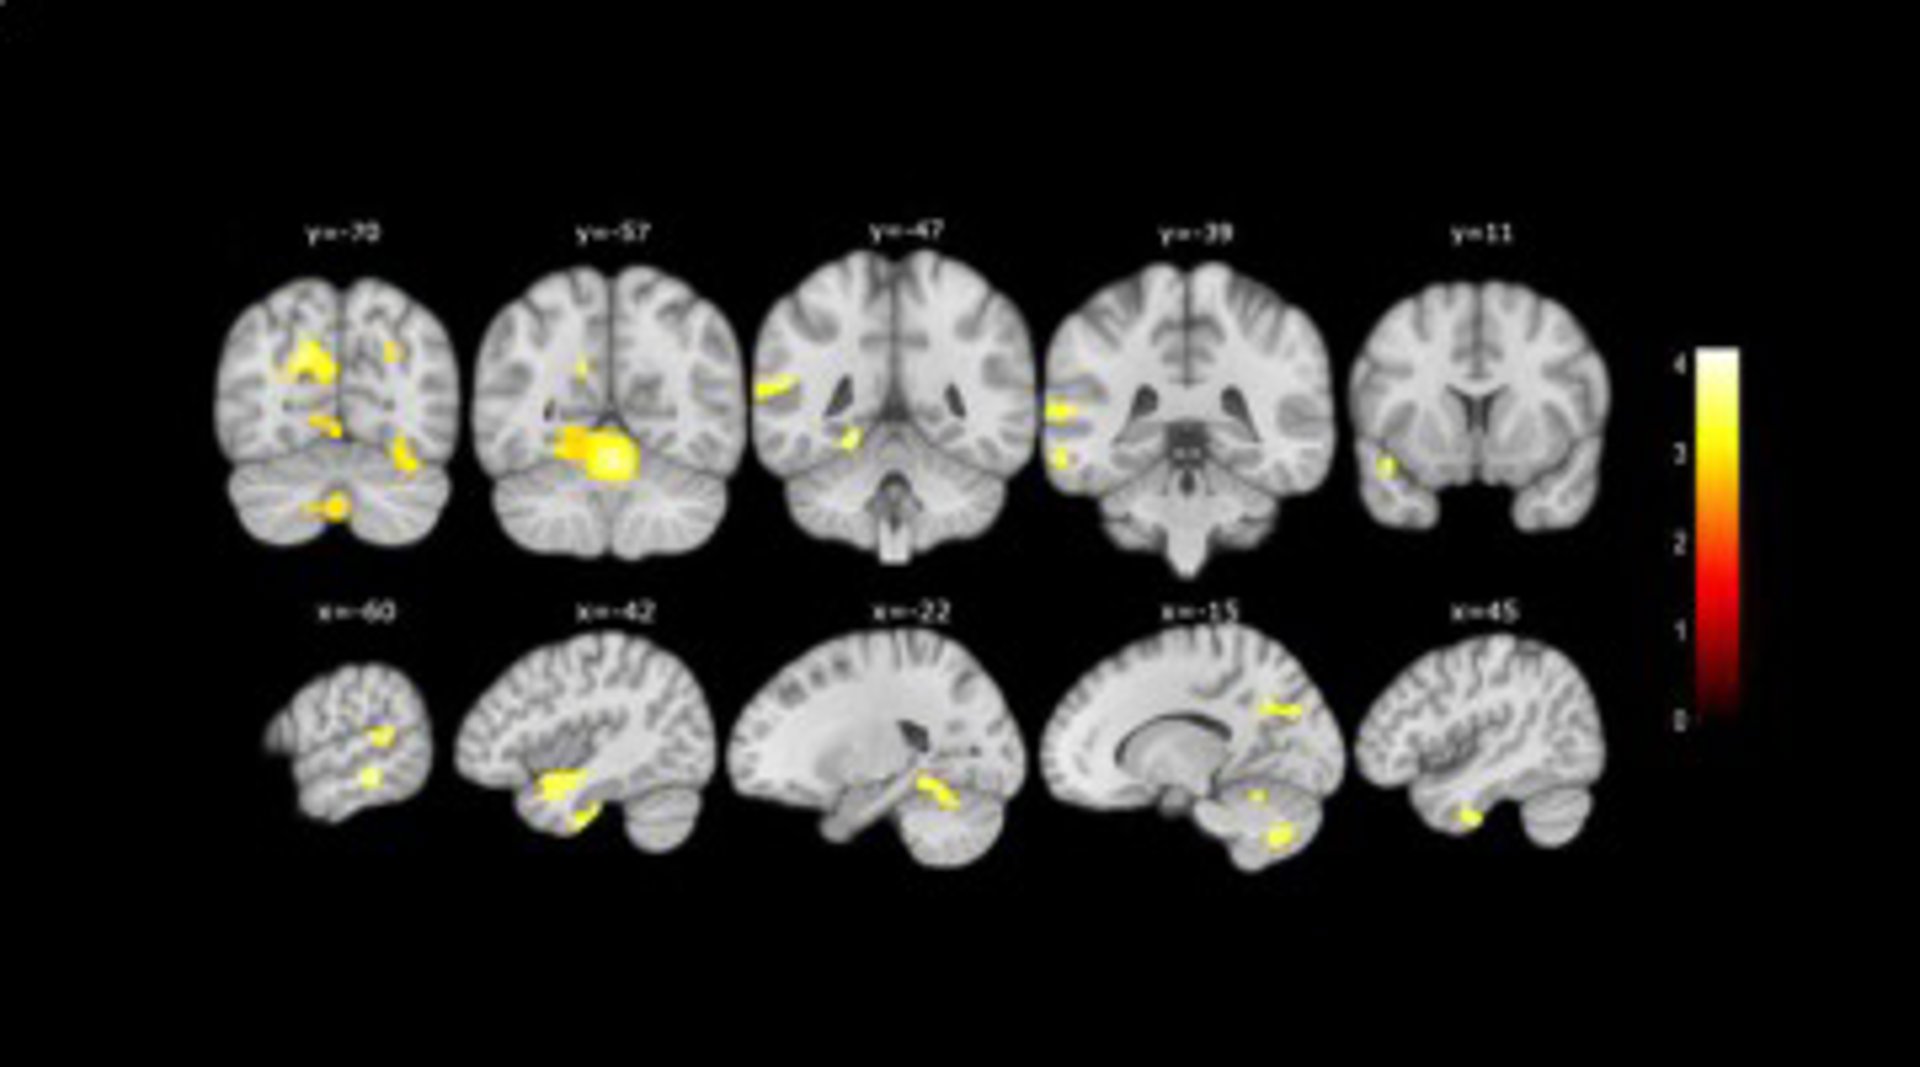

Además, gracias a la resonancia magnética realizada a un subgrupo de participantes, los investigadores también descubrieron que las personas que presentaban más de tres características asociadas a las quejas presentaban una mayor atrofia cerebral que los otros participantes con quejas pero con menos características asociadas.

MENOR VOLUMEN

En concreto, observaron un menor volumen en áreas cerebrales que se afectan en la enfermedad de Alzheimer, como son el hipocampo, el lóbulo temporal, el cerebelo y el precúneo.